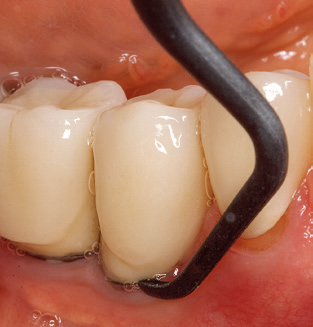

The current working concept for SPT

Fig. 4: Flexible probes with millimetre markings are recommended for the probing of dental implants (e.g. Colorvue Kit PCV11KIT6, Hu­Friedy). – Fig. 5a and b: A straight working tip (1P, W&H Dentalwerk Bürmoos GmbH) is a suitable instrument for use on all natural teeth. – Fig. 6: Curved working tips (3Pr/3Pl, W&H Dentalwerk Bürmoos GmbH) lend themselves to the processing of difficult-to-reach areas of the tooth and root surfaces (e.g. furcations). – Fig. 7: The tapered, hexagonal implant cleaning tip (1I, W&H Dentalwerk Bürmoos GmbH) permits atraumatic and efficient cleaning of the crown and abutment surfaces. – Fig. 8: Titanium and carbon curettes are suitable instruments for the manual cleaning of the implant surfaces.

Good illumination of the working field facilitates the process considerably. The system used by the authors achieves this thanks to a 5x LED ring integrated in the handpiece. Naturally, a range of working tips for different indications is also offered. A straight, universally employable tip is the basic instrument required for machine cleaning of natural teeth (Fig. 5a and b). Curved tips, which allow access to exposed furcations, are also available for hard-to-reach areas in the posterior region (Fig. 6).